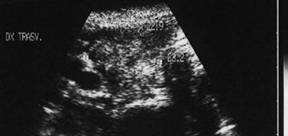

Lob stang, proiectie trasversala si longitudinala

Barbat de 55 ani. Formatiune nodulara voluminoasa ce ocupa 2/3 din lobul stang, hipoecogena, neomogenea, de 20 x 23 x 44mm(10 cc). Citoaspirata ecoghidata: carcinom midolar. Confirmat histologic.

Scintigrafia si CT aceluiasi pacient, metastaza laterocervicala stg ce impinge traheea spre dr.